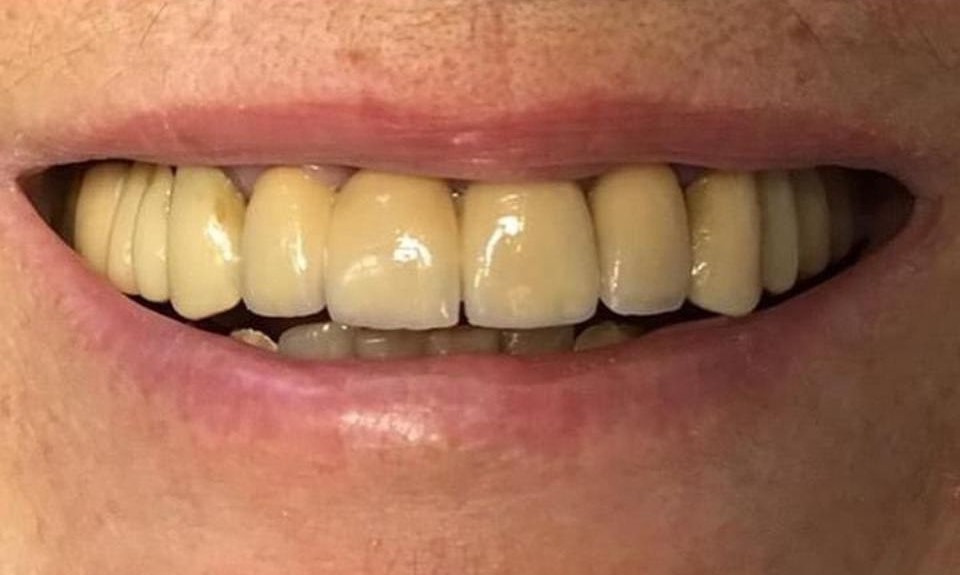

La riabilitazione fissa a carico immediato tipo full-arch e All-on-4 è una procedura odontoiatrica avanzata per ripristinare l’estetica e la funzionalità di un’intera arcata dentale (superiore o inferiore) utilizzando un numero ridotto di impianti dentali, solitamente quattro, che supportano una protesi fissa applicata immediatamente dopo l’intervento chirurgico. Grazie a questa tecnica, il paziente torna a casa con i denti fissi subito dopo l’intervento.